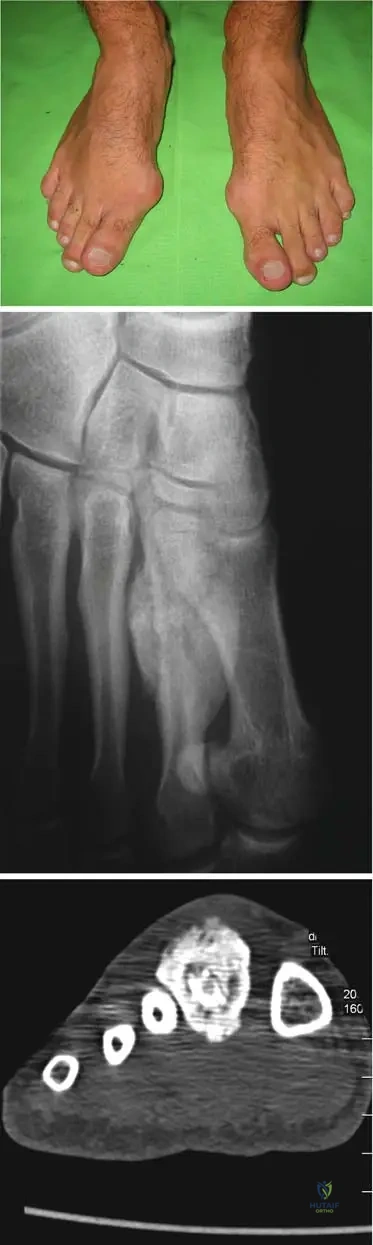

A 12-year-old boy presents with a 2-month history of left thigh pain, swelling, and intermittent fever. Physical examination reveals a tender, warm mass in the mid-diaphysis of the femur. Laboratory tests show elevated ESR and CRP. Radiographs show a large, destructive lytic lesion in the femoral diaphysis with a characteristic "onion skin" periosteal reaction and soft tissue mass. Biopsy confirms small round blue cells.

View Answer & Explanation

Correct Answer: D

Question 52